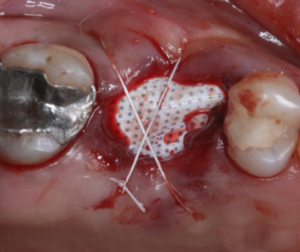

Vista oclusal do alvéolo suturado com fio de PFTE Cytoplast.